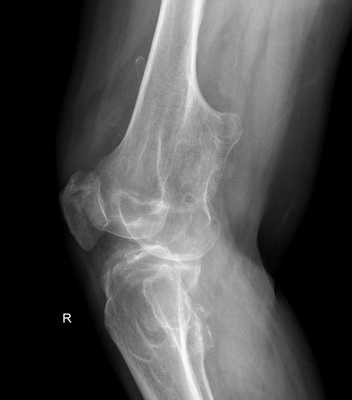

Чаще всего хрящевой экзостоз формируется на поверхности большеберцовой кости вблизи колена. Растущий нарост оказывает выраженное давление на четырехглавую бедренную мышцу и надколенник, в результате чего под деформированными тканями образуется слизистая сумка. Патология сопровождается сильным дискомфортом, а при большом размере нароста может происходить перелом кости и формирование ложного сустава. Иногда экзостоз коленного сустава поражает его внутреннюю капсулу, что приводит к значительному ограничению подвижности ноги.

В нашей клинике стандартным методом диагностики является рентгенологическое исследования. На рентгенограммах остеохондромы определяются как локальное выбухание кости. Все экзостозы исходят из кости на узкой или на широкой ножке. От этого зависит эволюция остеохондром и выбор тактики лечения.

Основным методом диагностики является рентген в 2-х проекциях. На снимках визуализируется только костная часть опухоли в виде новообразования с четкими границами и соединенного тонкой ножкой или толстым основанием с материнской костью. Также наблюдается истончение кортикального слоя кости, а сама остеохондрома часто имеет вид «цветной капусты» из-за участков обызвествлений в хрящевой шапочке.